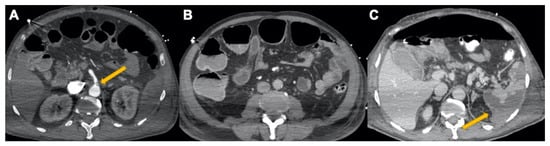

3.3. Abdominal Manifestations

2.3. Pulmonary Embolism